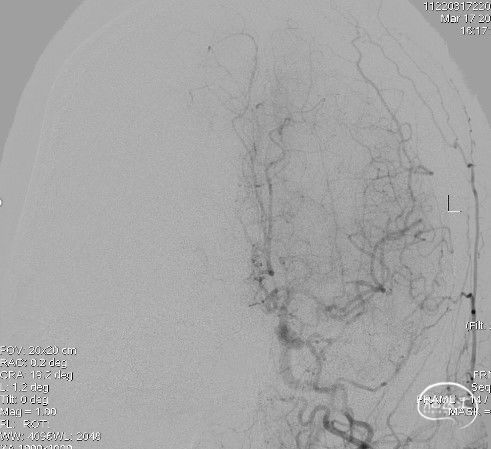

左颈内动脉:大脑前动脉通过前交通动脉向右侧代偿供血,左侧大脑中动脉分叉部分支闭塞。

左侧颈总动脉侧位: